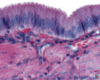

Trachea

H&E stain of smooth muscle